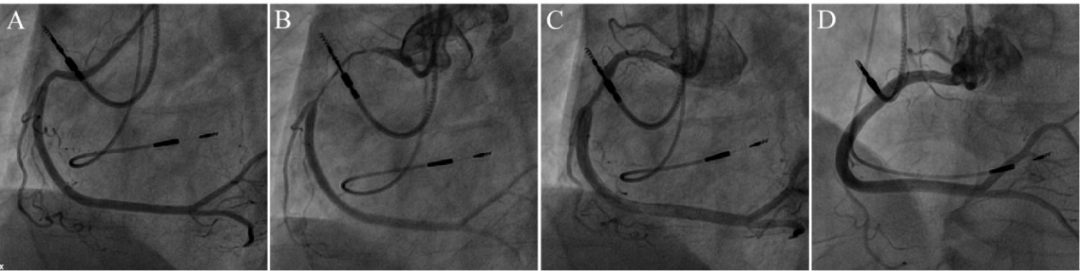

图1 右冠痉挛表现为冠脉细长

图9 导丝诱发冠脉痉挛。

前降支中段肌桥段可疑狭窄(A),拟行IVUS检查。导丝通过后肌桥段痉挛(B),注射硝酸甘油后缓解(C)。

图10 IVUS导管诱发冠脉痉挛。

前降支中段肌桥段可疑狭窄(A),行IVUS检查后肌桥段痉挛(B),注射硝酸甘油后缓解(C)。

图11 球囊诱发冠脉痉挛。

右冠弥漫性病变,远段最重狭窄95%(A),药物球囊处理后弥漫性变细(B),注射硝酸甘油后缓解(C)。

图12 导管深插诱发顽固性痉挛。

JR4造影导管深插至右冠(A),退至开口造影提示近段严重狭窄(B),冠脉内注射硝酸甘油200μg×3次只有部分缓解(C),继续推注200μg×2次后基本缓解(D)。说明部分患者强刺激后痉挛比较持久。该病人并无血管痉挛的临床表现,术后不需要抗痉挛治疗。